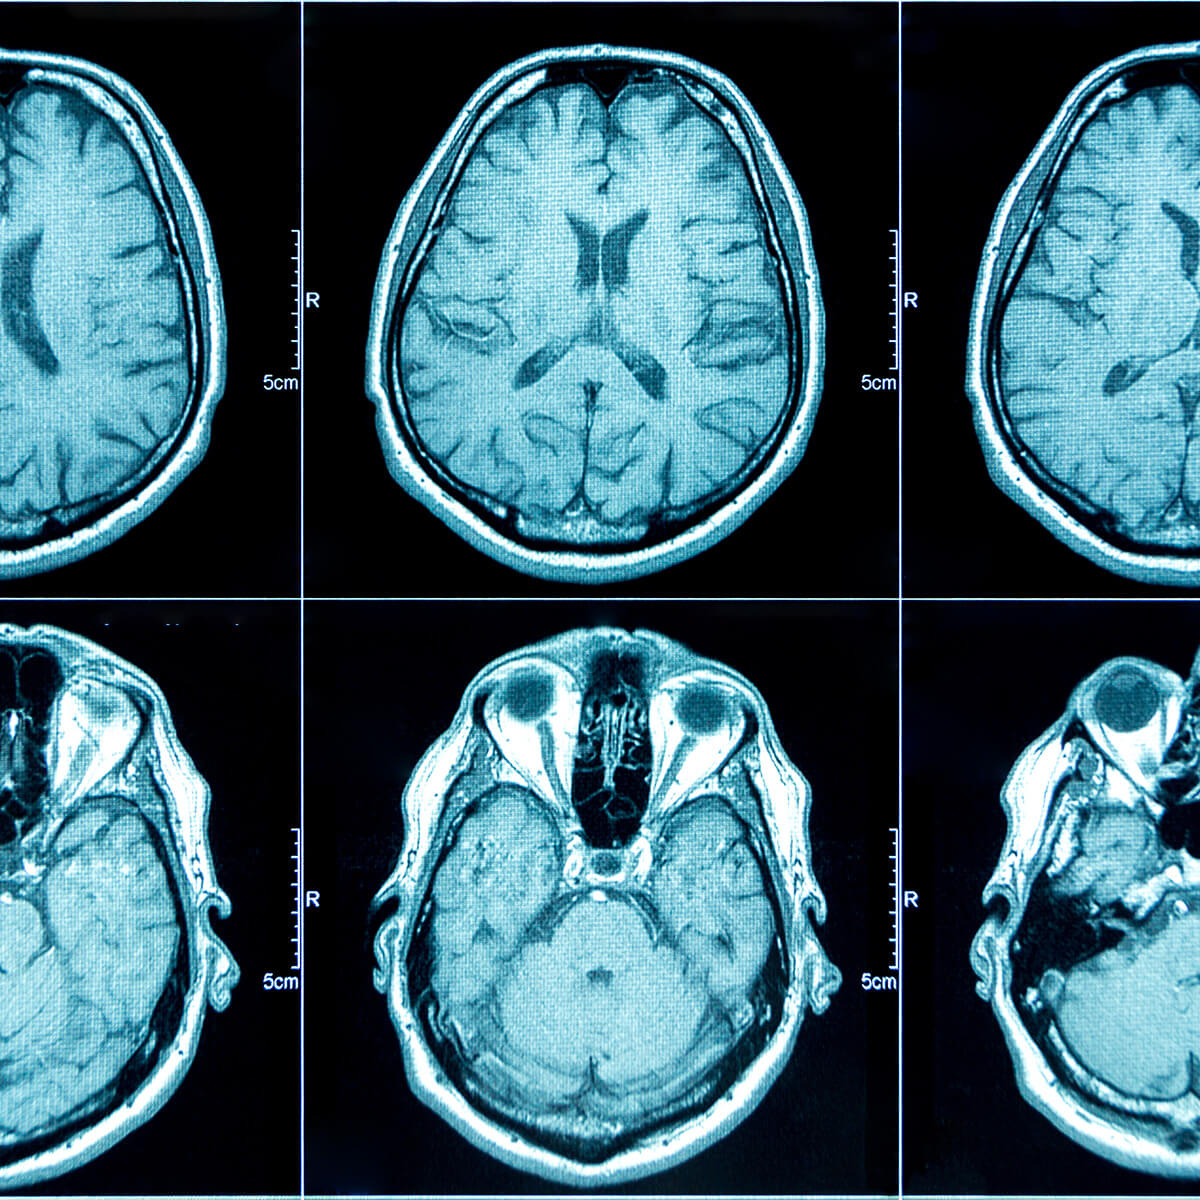

Magnetic Resonance Imaging (MRI)

Magnetic Resonance Imaging uses a large magnet positioned around the person to produce a magnetic field in the patient’s body. Precise two-or three-dimensional images are produced, providing doctors with detailed information about the brain’s structures.